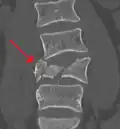

A burst fracture of L4 as seen on CT A burst fracture of L4 as seen on CT